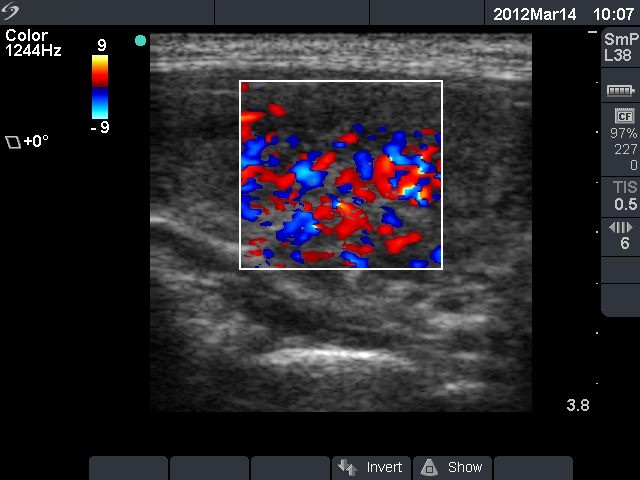

First examination (first row):

Clinical presentation: a 17-year-old girl who has been treated for hyperthyroidism for 2 years. She had no complaints.

Palpation: no abnormality.

Functional state: euthyroidism on daily 10 mg methimazole with TSH 2.14 mIU/L, FT4 13.2 pM/L.

Ultrasonography: the thyroid was echonormal with a hyperechogenic lesion in the central part of the right lobe. The vascularization was a little bit increased.Suggestion: discontinuation of thyrostatic therapy and follow-up examination 6 months later.